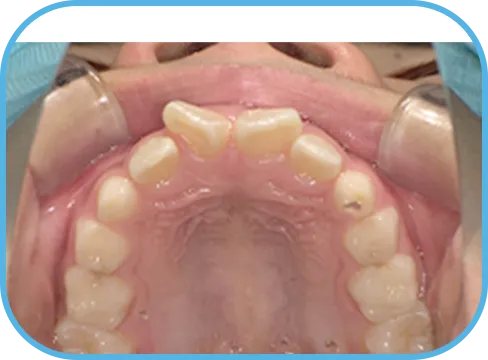

• Before

• 上 顎

治療前上顎からの歯の様子

主 訴

前歯がでている、噛み合わせが深い

治療内容

インビザライン・ファースト

治療期間

10か月

治療費(税別)

450,000円+診断料30,000円

リスク・副作用

• 親知らずの影響や加齢などによって、凸凹が生じる可能性があります。

• 治療の初期段階では痛みや不快感が生じやすくなりますが、1週間前後で慣れます。

• 顎の成長発育によって、噛み合わせや歯並びが変化する可能性があります。

• 状況により当初予定した治療計画を変更する可能性があります。